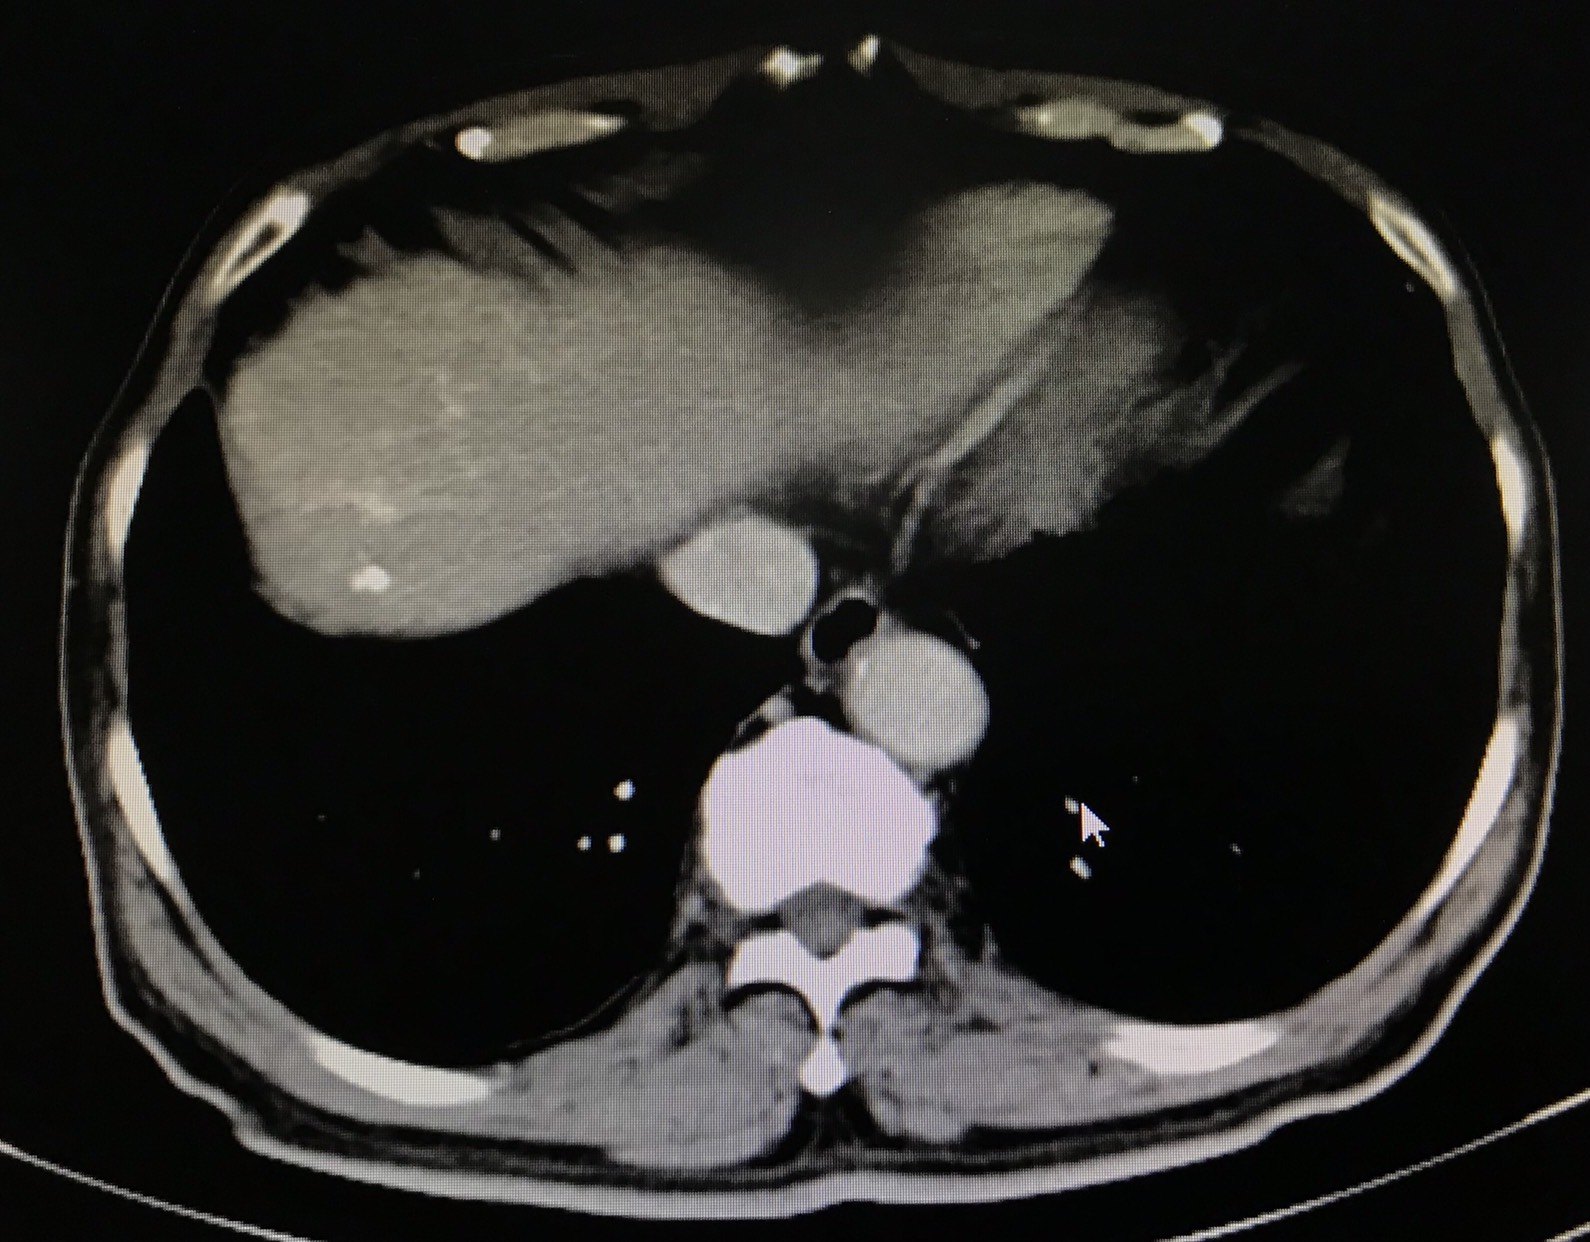

肝静脉癌栓的氩氦刀冷冻消融治疗案例分享

1590x1242 - 299KB - JPEG

1624x1242 - 480KB - JPEG

1292x1242 - 313KB - JPEG